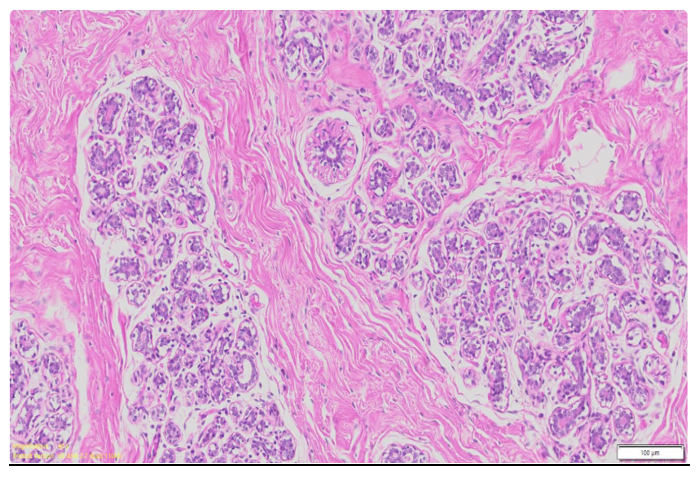

A significant portion of the breast is made up of adipose tissue (Figure 1), especially in post-adolescent, non-lactating females.9 Adipocytes not only determine breast volume and contour but also serve endocrine functions, producing adipokines (e.g., leptin, adiponectin, resistin) and cytokines that influence local immune responses and hormonal signaling. In healthy tissue, adipose deposits are well-vascularized, without necrosis, inflammation, or fibrosis. Their presence also contributes to the elasticity and pliability of the breast, factors critical for surgical manipulation and reconstructive applications.10

Figure 1 Microscopic cross section of the mammary tissue.33

This image shows the histological architecture of mammary tissue, highlighting ducts, adipose tissue, and connective stroma.